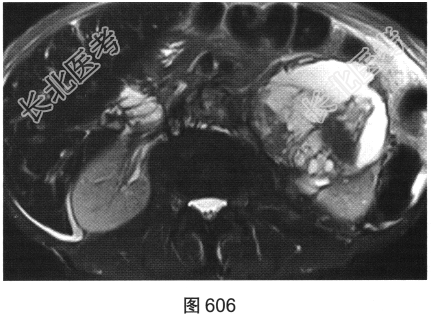

- [材料题] 患者女性,85岁,腹主动脉瘤破裂手术修复后,腹部疼痛。患者行腹部CT检查,见图603~图607。

- 简答题3、患者进一步行MRI检查,请对MRI影像特征描述一下。